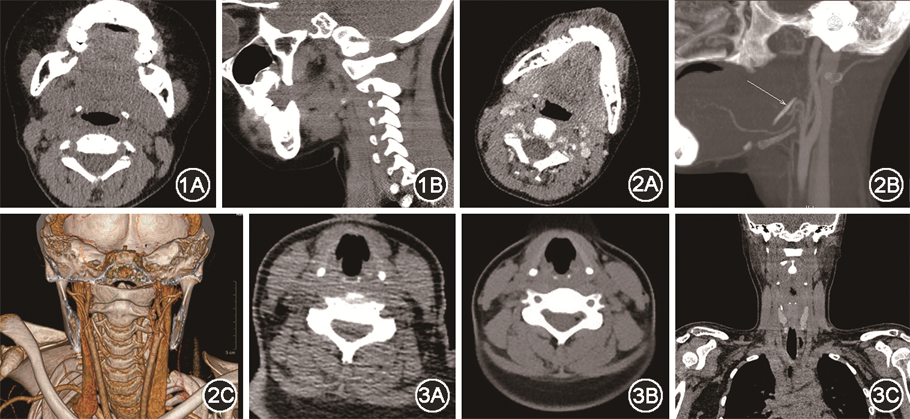

例1,患儿男,8岁,因“误咽鸡骨头3 d”来我院急诊就诊,携带外院颈部CT示右侧咽旁近食道入口异物,患儿3 d前进食鸡肉后出现咽部疼痛,进食稍不适,给予急诊行电子鼻咽喉镜检查示咽喉部未见明显异物。遂急诊拟“食道异物”收住入院,准备全身麻醉下手术取异物。查体:神志清晰,呼吸平顺,口唇黏膜无发绀,颈前区无明显压痛,无颈部皮下气肿,口咽部未见明显异物。入院后准备急诊行咽旁探查术,术前患儿诉咽喉部疼痛较前好转,遂给予颈部CT平扫+三维重建检查,示右侧茎突舌骨韧带走行区域见一条状致密影,长度约19.7 mm,边界光整清晰,周围软组织未见明显肿胀和积气,考虑茎突舌骨韧带钙化可能(图1,2)。遂再次询问病史,患儿诉进食鸡肉为鸡胸肉,无骨性物质,且咽喉部疼痛已缓解,结合CT,考虑患儿为茎突舌骨韧带钙化误诊食道异物,给予出院。出院后1个月电话随访,患儿家长诉患儿咽喉部无明显异常症状。

例2,患儿女,16岁,因“咽喉异物感0.5 d”来我院急诊就诊,诉午餐时进食鱼圆后出现咽喉异物感。给予患儿急诊CT检查,示食道上段走行区可见条状致密影,考虑食道上段异物可能(图3A),遂急诊拟“食道异物”收住入院。查体:神志清晰,呼吸平顺,口唇黏膜无发绀,颈前区无明显压痛,无颈部皮下气肿,口咽部未见明显异物。住院后次日全身麻醉下行食道镜检查术,全麻满意后,常规消毒铺单,助手抱头取Boyce位。食道镜经口咽正中向下插入,见杓状软骨后,向前轻推喉部,进入食道,检查食道后食道走行未见明显异物,术后安返病房。术后给予复查CT,示咽部后方C5水平点状致密影,较前位置相仿,考虑杓状软骨钙化可能(图3B、3C)。术后患儿诉无明显咽喉不适症状,结合CT,考虑患儿为杓状软骨钙化误诊食道异物,给予出院。出院后1个月电话随访,患儿家长诉患儿咽喉部无明显异常症状。

在患儿1中,术前复查CT发现患儿茎突舌骨韧带钙化,考虑为茎突舌骨韧带骨化。茎突由胚胎第2鳃弓的Reichert软骨发育形成,其前下基部发育成舌骨,基部两端有一条软骨链与颞骨相连,软骨链有4段,骨舌段、茎舌段、角舌段(茎突舌骨韧带)和下舌段,这些节段可以骨化形成骨性融合,角舌段骨化,则形成茎突舌骨韧带骨化[4]。因骨化部位可刺激周围的组织和咽部黏膜,因此其临床症状主要为咽部疼痛和咽异物感,因与食道入口异物症状相似,导致了本例误诊的发生,茎突舌骨韧带骨化临床上较为少见,基本发生与成人,儿童极为少见[5]。在患儿2中,术后复查CT示杓状软骨钙化。喉软骨的钙化绝大多数发生于21岁以后的成年人[6],在儿童时期钙化发生较少。在骨化早期甲状软骨的上角及软骨板的边缘部,常呈短条状致密影,且靠近食道,易误诊异物;杓状软骨的小点状钙化,也与异物相似,导致误诊;环杓关节的边缘的早期骨化,呈短条状或弧形致密阴影,也易误诊食道异物。